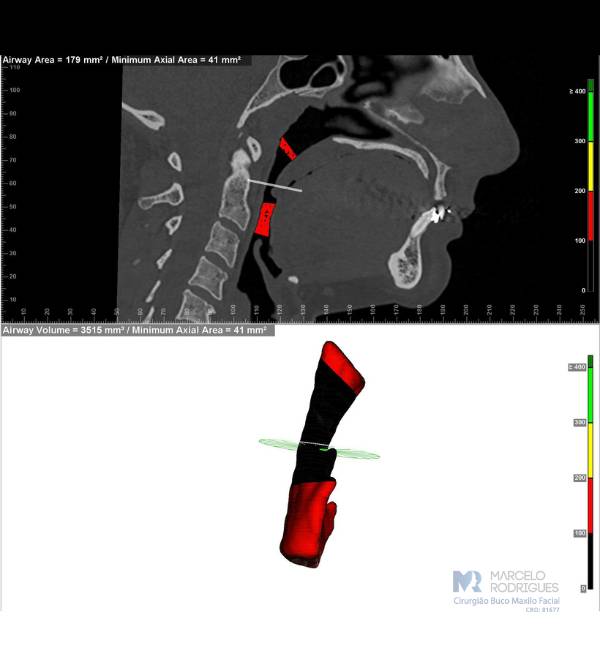

A síndrome da apneia obstrutiva do sono é uma condição na qual ocorrem problemas significativos de obstrução das vias aéreas durante o sono. A causa mais comum dessas obstruções envolve obstrução nasal e/ou diminuição do espaço das vias aéreas orofaríngeas (espaço entre a parte posterior da língua e a parte posterior da garganta).

Existem tratamentos clínicos com uso de aparelhos chamados CPAP, tratamentos odontológicos com uso de aparelhos intra-orais, e quando necessário, tratamentos cirúrgicos mais complexos.